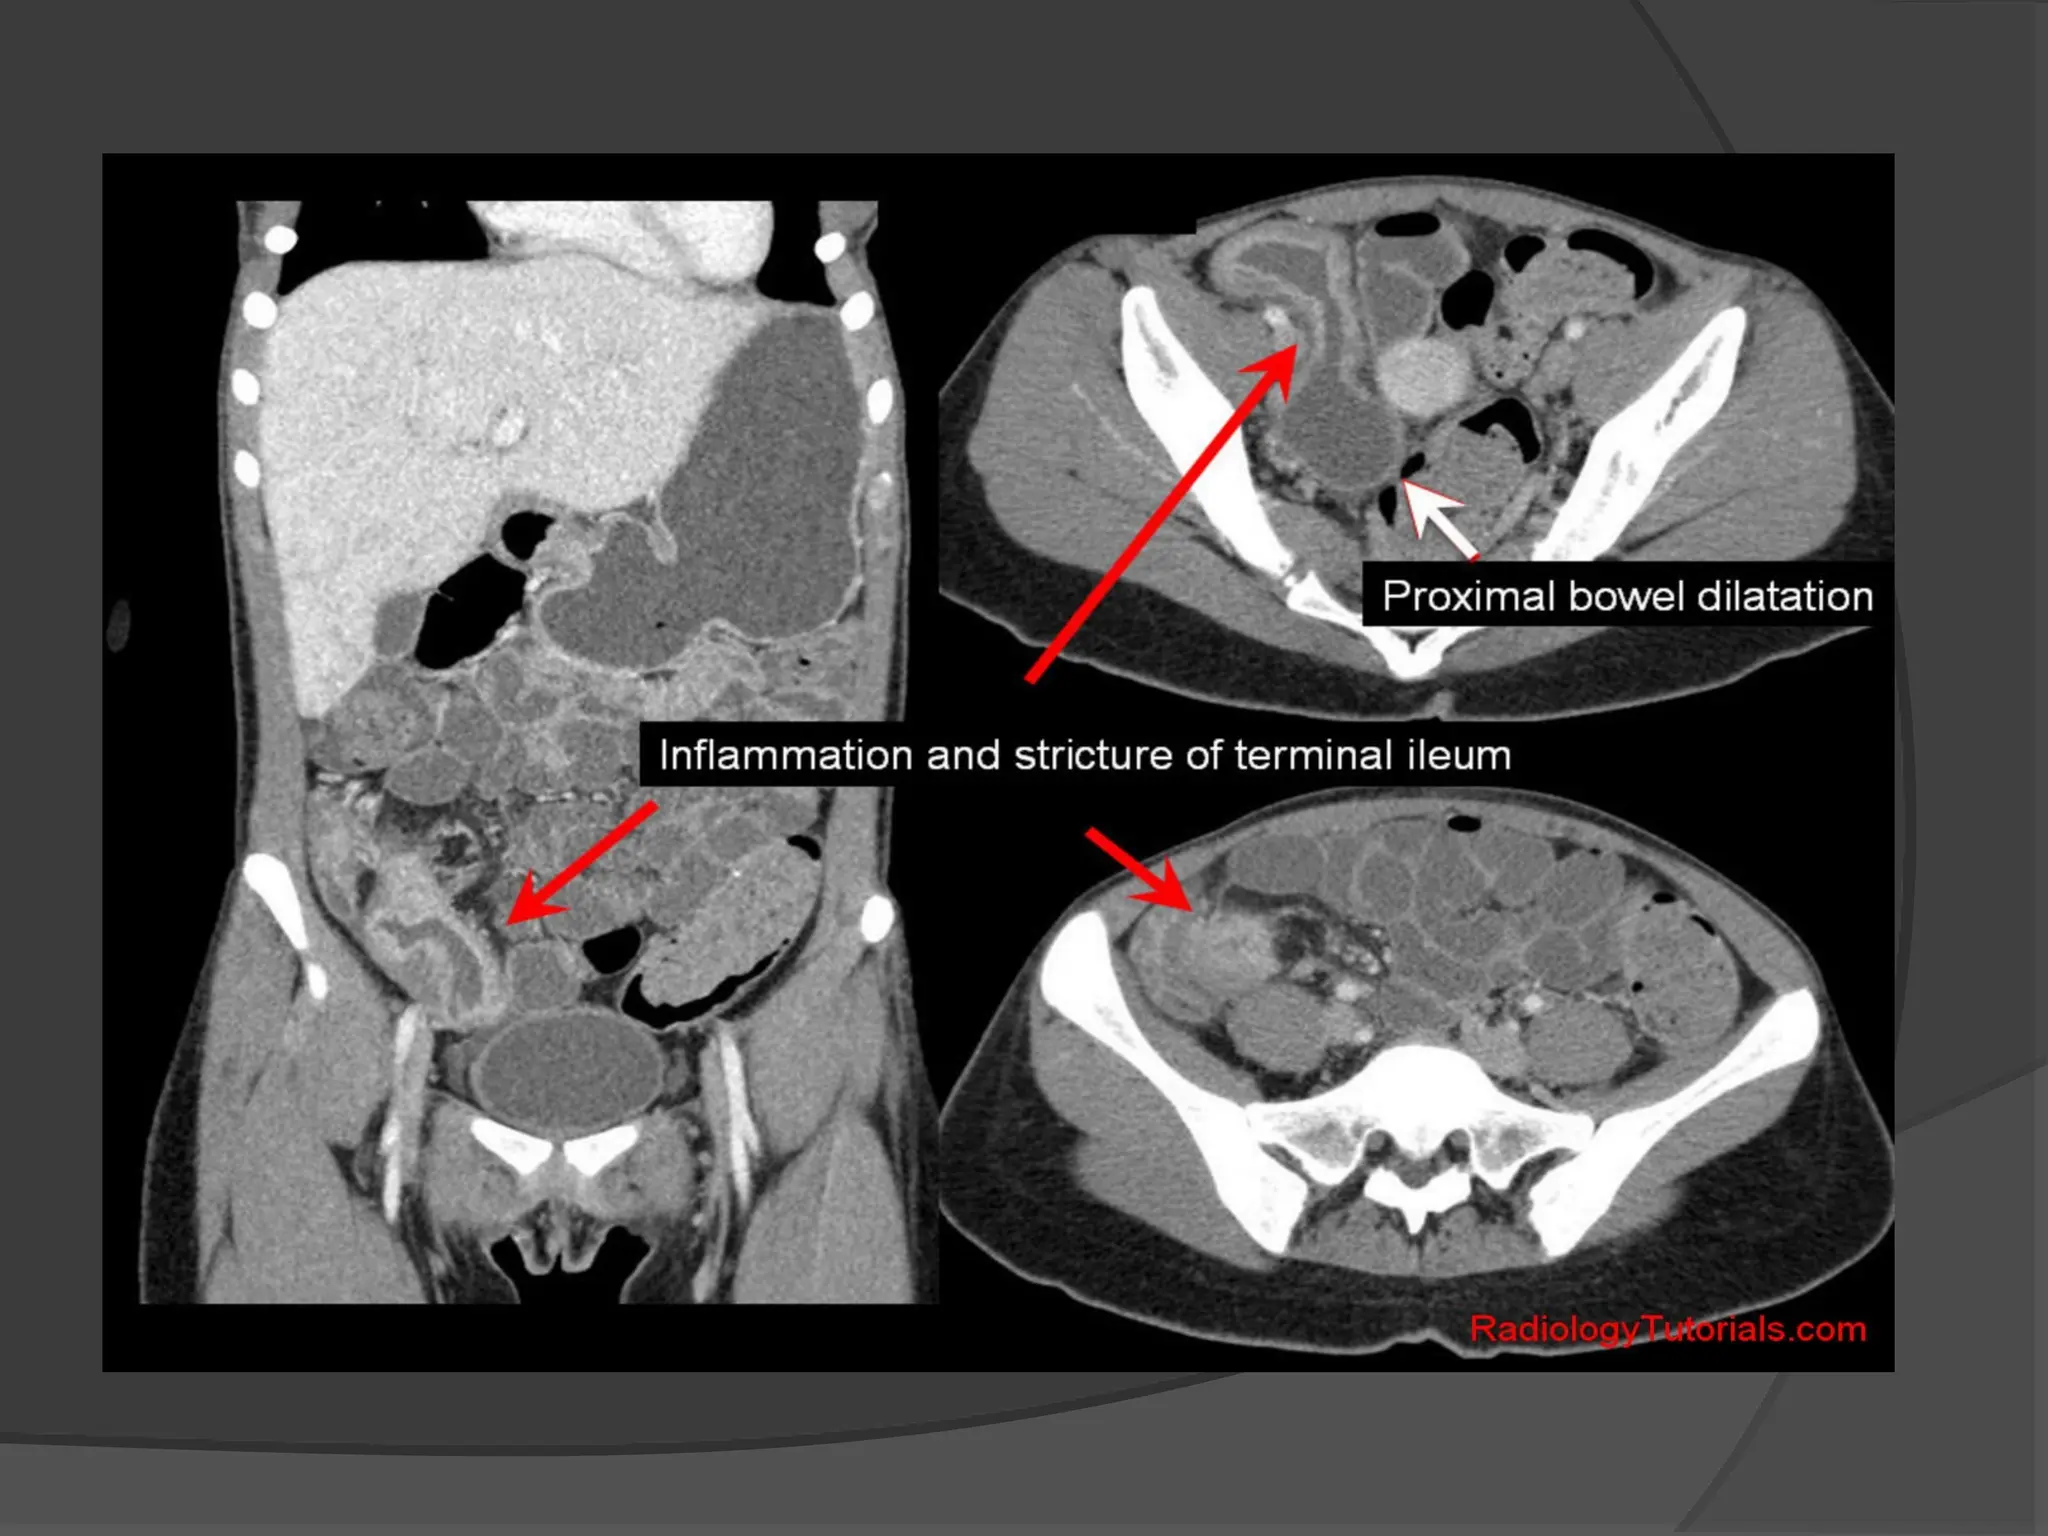

Obstruction from Enteric Strictures

 Small bowel strictures usually occur secondary

to Tuberculosis or Crohn’s disease.

In Crohn's disease, strictureplasty may be

considered in the presence of short multiple

strictures

.